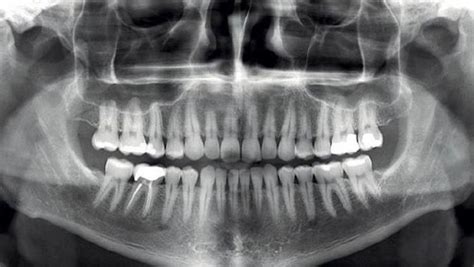

La ortopantomografía, también conocida como radiografía panorámica o panorámica dental, es una herramienta fundamental en odontología y ortodoncia. Proporciona una imagen bidimensional de toda la mandíbula, los dientes y las estructuras circundantes en una sola toma.

Lo que define una radiografía panorámica es que da una visión panorámica de las estructuras dentales, óseas y, en menor medida, de tejidos blandos del área de los maxilares. El otro nombre de la radiografía panorámica: ortopantomografía, recoge la otra característica de las radiografías panorámicas: es una proyección ortostática. Quiere decir “recto”. Los maxilares son curvos, como esta radiografía es en dos dimensiones, lo que hace la ortopantomografía es “aplanar” los maxilares.

Las radiografías panorámicas dan mucha información general. Pero hemos de tener en cuenta que las medidas no son reales. Pero más importante que la magnificación global es saber que sentido “lateral” las medidas no son reales (la zona de los premolares está reducida). En resumen: la radiografía panorámica u ortopantomografía es una radiografía dental de toda la boca que da mucha información del conjunto con muy poca radiación y a un precio barato.